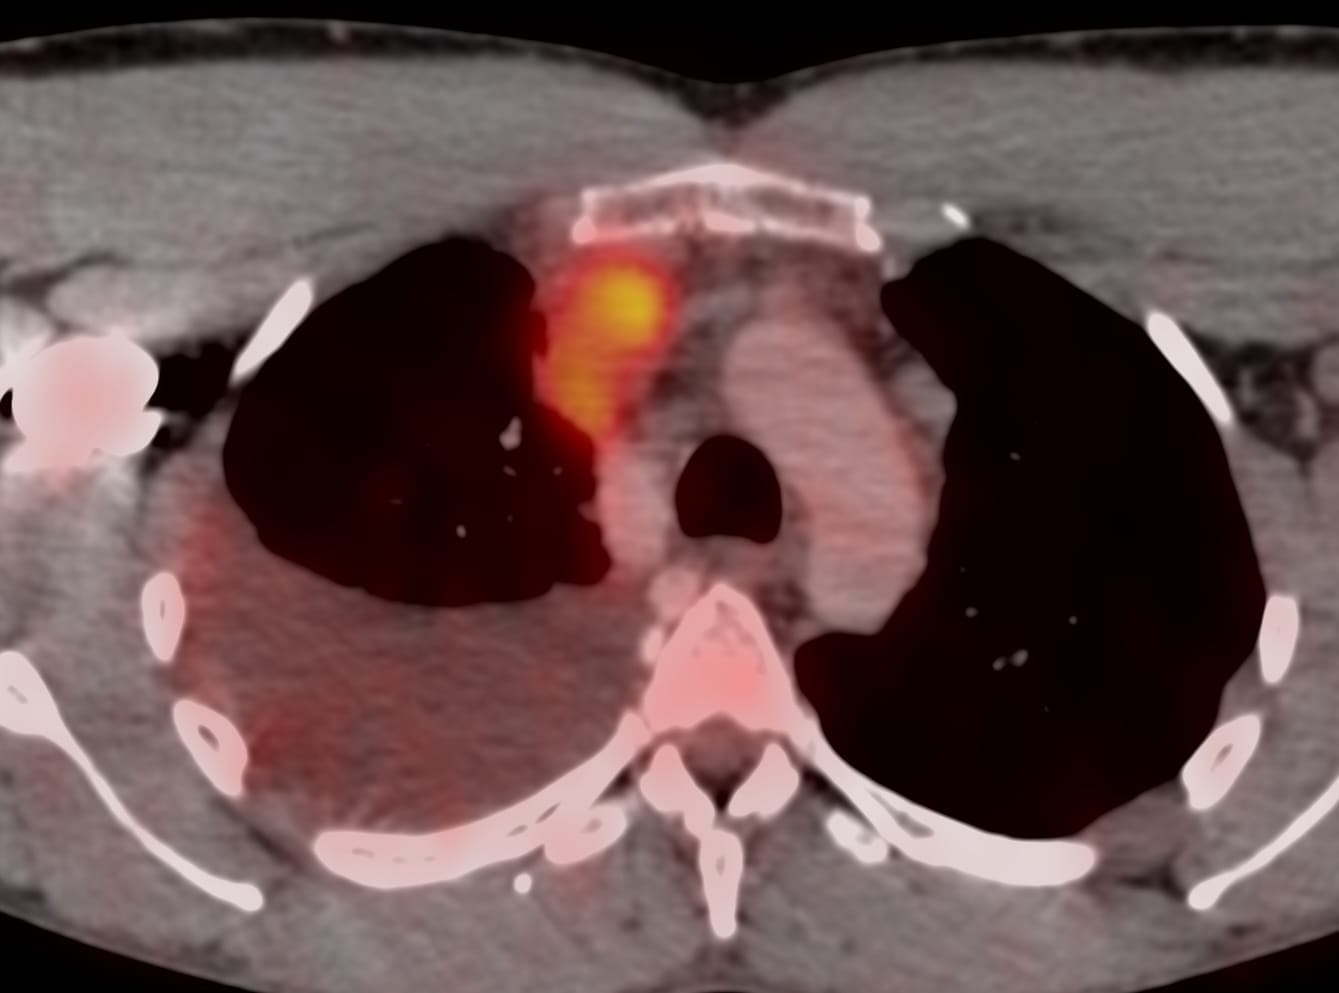

Case 18: 31-years old with chest pain and SVC syndrome